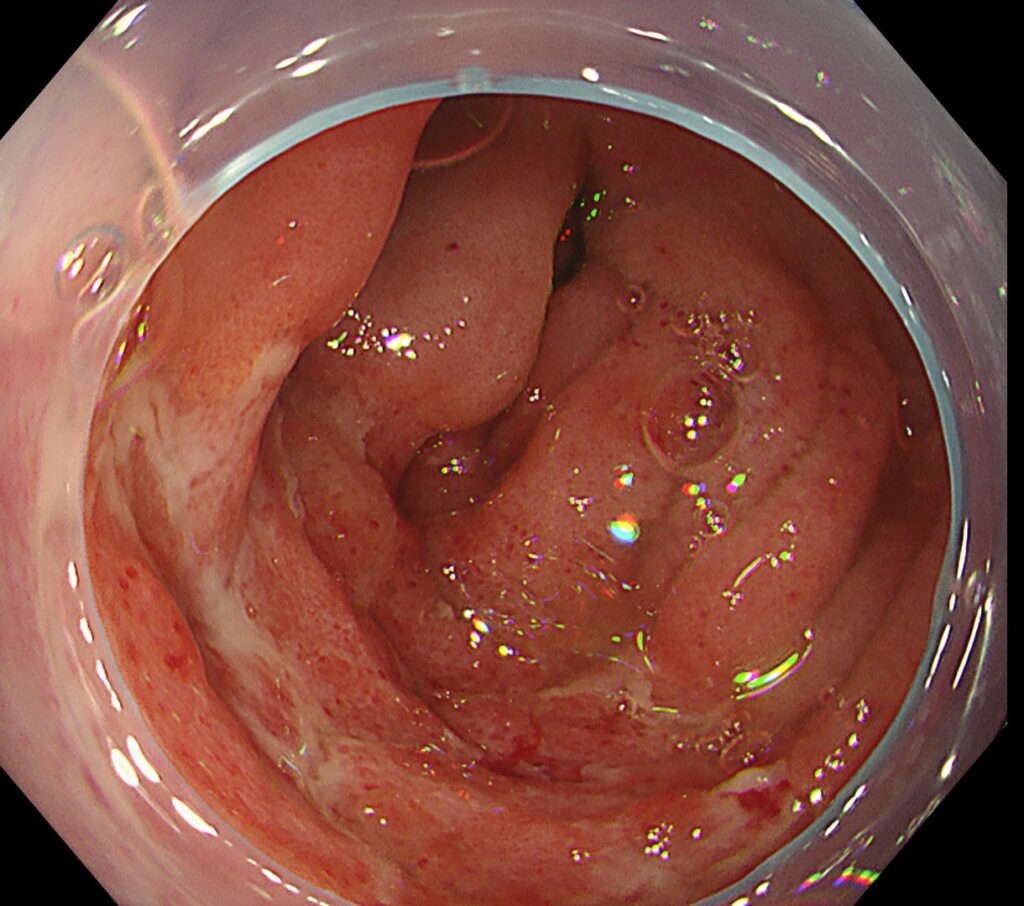

加えて、上行結腸はびまん性に斑状発赤を認めます。